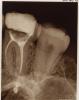

Sonrisa Опубликовано 29 августа, 2009 Поделиться Опубликовано 29 августа, 2009 (изменено) Здравствуйте, уважаемые Доктора!Более месяца назад был депульпирован 16-й зуб (пульпит). До сих пор беспокоит умеренно выраженная боль при накусывании и болезненная перкуссия. Каналы обтурированы одной пастой (форфенан?) Самопроизвольных болей нет. Может ли столь длительная болезненность зуба при мех. воздействии быть вызвана только лишь заапикальным выведением пасты? Ну и, конечно, не может не интересовать вопрос о том насколько ухудшит прогноз обломок инструмента (судя по всему каналонаполнителя) и, соответственно, "недообтурированность" данного канала.И, вообще, что еще интересного видите и как долго сможет прожить просуществовать моя труженница шестерка?Снимок во вложении.Заранее благодарна.С уважением. Изменено 29 августа, 2009 пользователем Sonrisa Ссылка на комментарий

Bier Опубликовано 29 августа, 2009 Поделиться Опубликовано 29 августа, 2009 так у вас инструмент в канале сломан, канал не запломбирован до конца. Вот и болит. Ссылка на комментарий

annda Опубликовано 29 августа, 2009 Поделиться Опубликовано 29 августа, 2009 (изменено) так у вас инструмент в канале сломан, канал не запломбирован до конца. Вот и болит.Там и третьего канала не видать(запломбированного).Возможно,наложился при съёмке,а возможно и...Про четвёртый вообще молчу.Прогноз не очень... Изменено 29 августа, 2009 пользователем annda Ссылка на комментарий

АНРОША Опубликовано 29 августа, 2009 Поделиться Опубликовано 29 августа, 2009 Bier, annda +1, а также полкило силера за апексом... доктор сделал все, что мог... Ссылка на комментарий

zybnaya feya Опубликовано 30 августа, 2009 Поделиться Опубликовано 30 августа, 2009 (изменено) Спасибо. Я и сама понимаю, что обнадеживать меня, увы, нечем. Перелечивать стоит? Есть еще и такой снимок, если на нем можно увидеть третий канал... Да видно и третий,совершенно пустой канал, и поломанный инструмент можно вытащить и каналы перелечить-это наименьшие проблемы. Непрогнозируимо очень большое выведение пасты за пределы корня и как оно себя поведет после того,когда восстановиться коронковая часть зуба и пойдет полноценная нагрузка на него(а возможно и перегруз).Пасту от туда уже не вымыть никак. Так что решайте сами-или работа без гарантии,или удаление и имплантация Изменено 30 августа, 2009 пользователем zybnaya feya Ссылка на комментарий